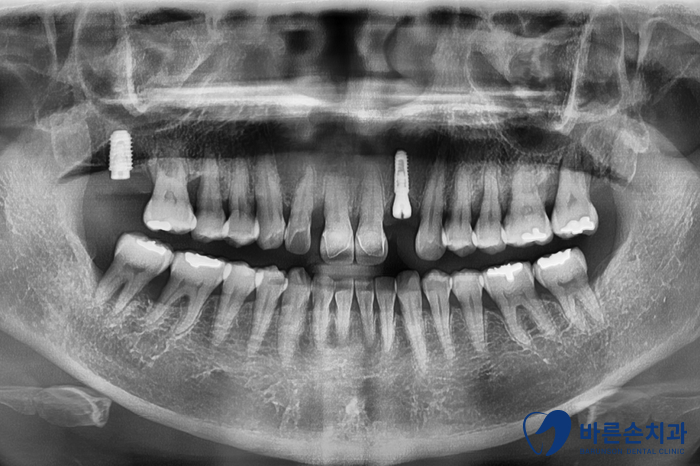

Before 25.05.16

이미 상실되어 있는 어금니와 함께 앞니 임플란트를 가지런히 심었습니다.

앞니 임플란트는 자주 보이는 부분이기에,

잇몸이 내려가지 않도록 식립하는게 관건입니다.

잇몸이 많이 내려가면, 심미적으로 좋지 않거든요.